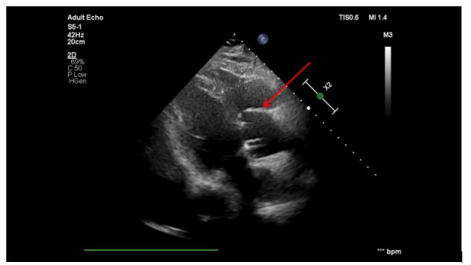

Echocardiography revealed a dilated aortic root (50 mm), preserved myocardial contractility, and an ejection fraction of 55%. A significant leak from the aorta into the right atrium was identified (Figure. 1). Computed tomography confirmed contrast leakage from the noncoronary sinus into the right atrium (Figure. 2). An anatomical anomaly was also observed, with the right coronary artery originating just above the ostium of the left coronary artery. Coronary angiography showed no significant stenoses.

Figure 1: Echocardiographic image before surgery. The arrow indicates the site of the aneurysm rupture into the right atrium.